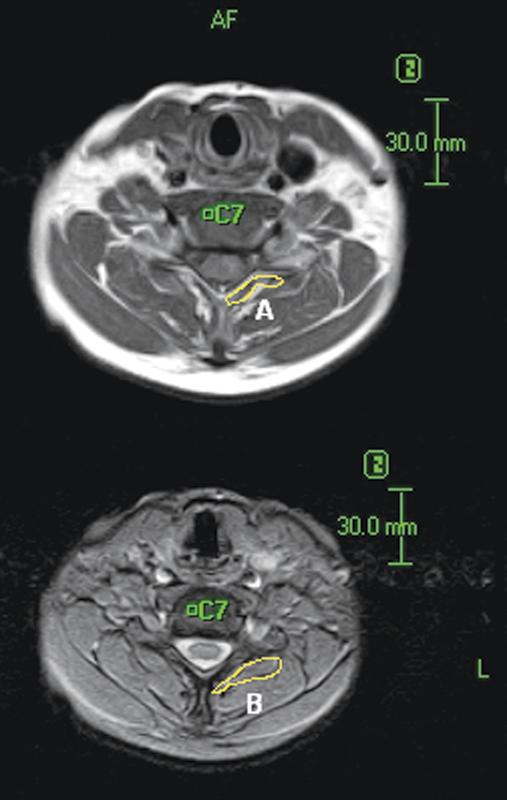

The alignment and mobility of the cervical spine is influenced by factors related to the vertebral bodies, intervertebral discs, ligaments, facet joints, and muscles. Few reports have described the role played by the paraspinal muscles in cervical spine mobility. In this study, we investigate the relationship between fatty degeneration of the paraspinal muscles and cervical motion as assessed with kinetic magnetic resonance imaging (kMRI). One hundred eighty-eight symptomatic patients underwent cervical kMRI in neutral, flexion, and extension positions. We quantified cervical paraspinal muscle fatty infiltration and measured angular variation and translational motion at each cervical level, and the global Cobb angle. Cervical paraspinal muscle fatty degeneration demonstrated a pattern in which C3 and C7 had significantly more fatty infiltration than C4, C5, and C6. Additionally, when the normal group was compared with the fatty degeneration group with respect to angular variation, translational motion, and Cobb angle, no significant differences were found except in angular variation at the C3-C4 level. In conclusion, we found a significantly larger quantity of fatty degeneration in the paraspinal muscles at C3 and C7 than the middle cervical levels. Also, we demonstrate that fatty degeneration does not significantly affect cervical lordotic alignment or mobility characteristics.